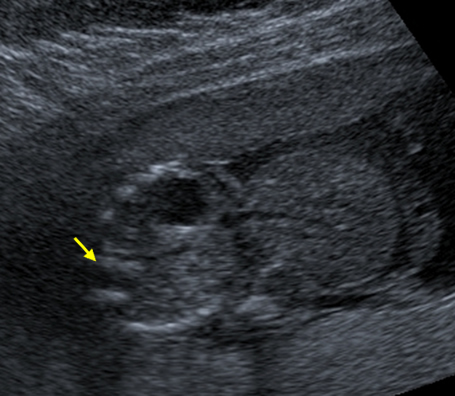

A long axis scan through the fetus shows the herniated liver coming from the anterior abdominal wall of the fetus. The fetal limbs, abdomen and head can also be seen.